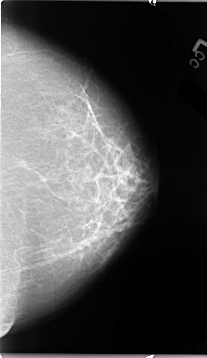

B_3068_1.LEFT_MLO

B_3068_1.LEFT_CC

LEFT_MLO LINES 4632 PIXELS_PER_LINE 2832 BITS_PER_PIXEL 12 RESOLUTION 50 NON_OVERLAY